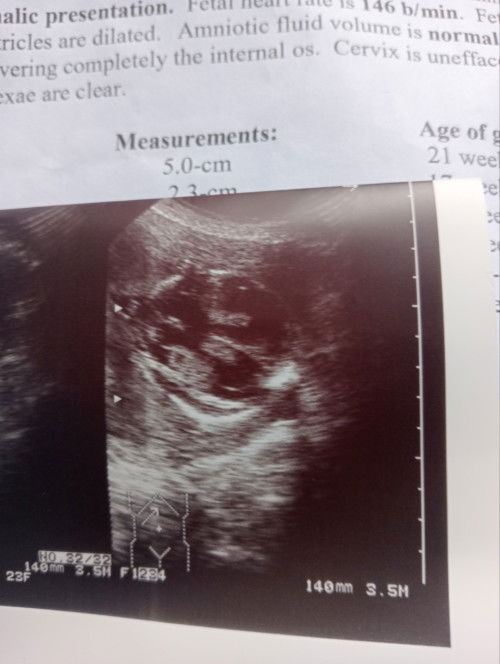

May sinabi ba silang malaki ulo ng baby mo? O opinion mo lang yan base sa ultrasound pics? Wag mag marunong. Mababaliw ka ng walang rason.

pls ask you OB sa explaination. di namin masasabing malaki o maliit kung yan lang babatayan.

Wala po ba sinabi OB niyo or yung Sono? Sila lang kase nakakaalam niyan eh.